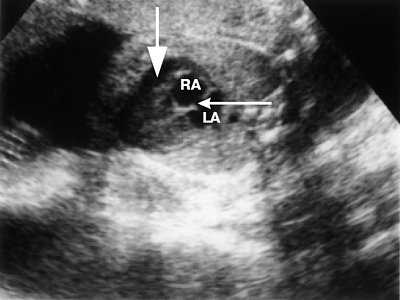

Рис. 1. Четырехкамерное сечение сердца плода в 30 недель гестации. Опухоль сердца прорастает миокард задней стенки левого желудочка, межжелудочковую перегородку. Межпредсердная перегородка уплотнена, овальное окно не функционирует (стрелка).

LA - левое предсердие, RA - правое предсердие, VS - межжелудочковая перегородка.